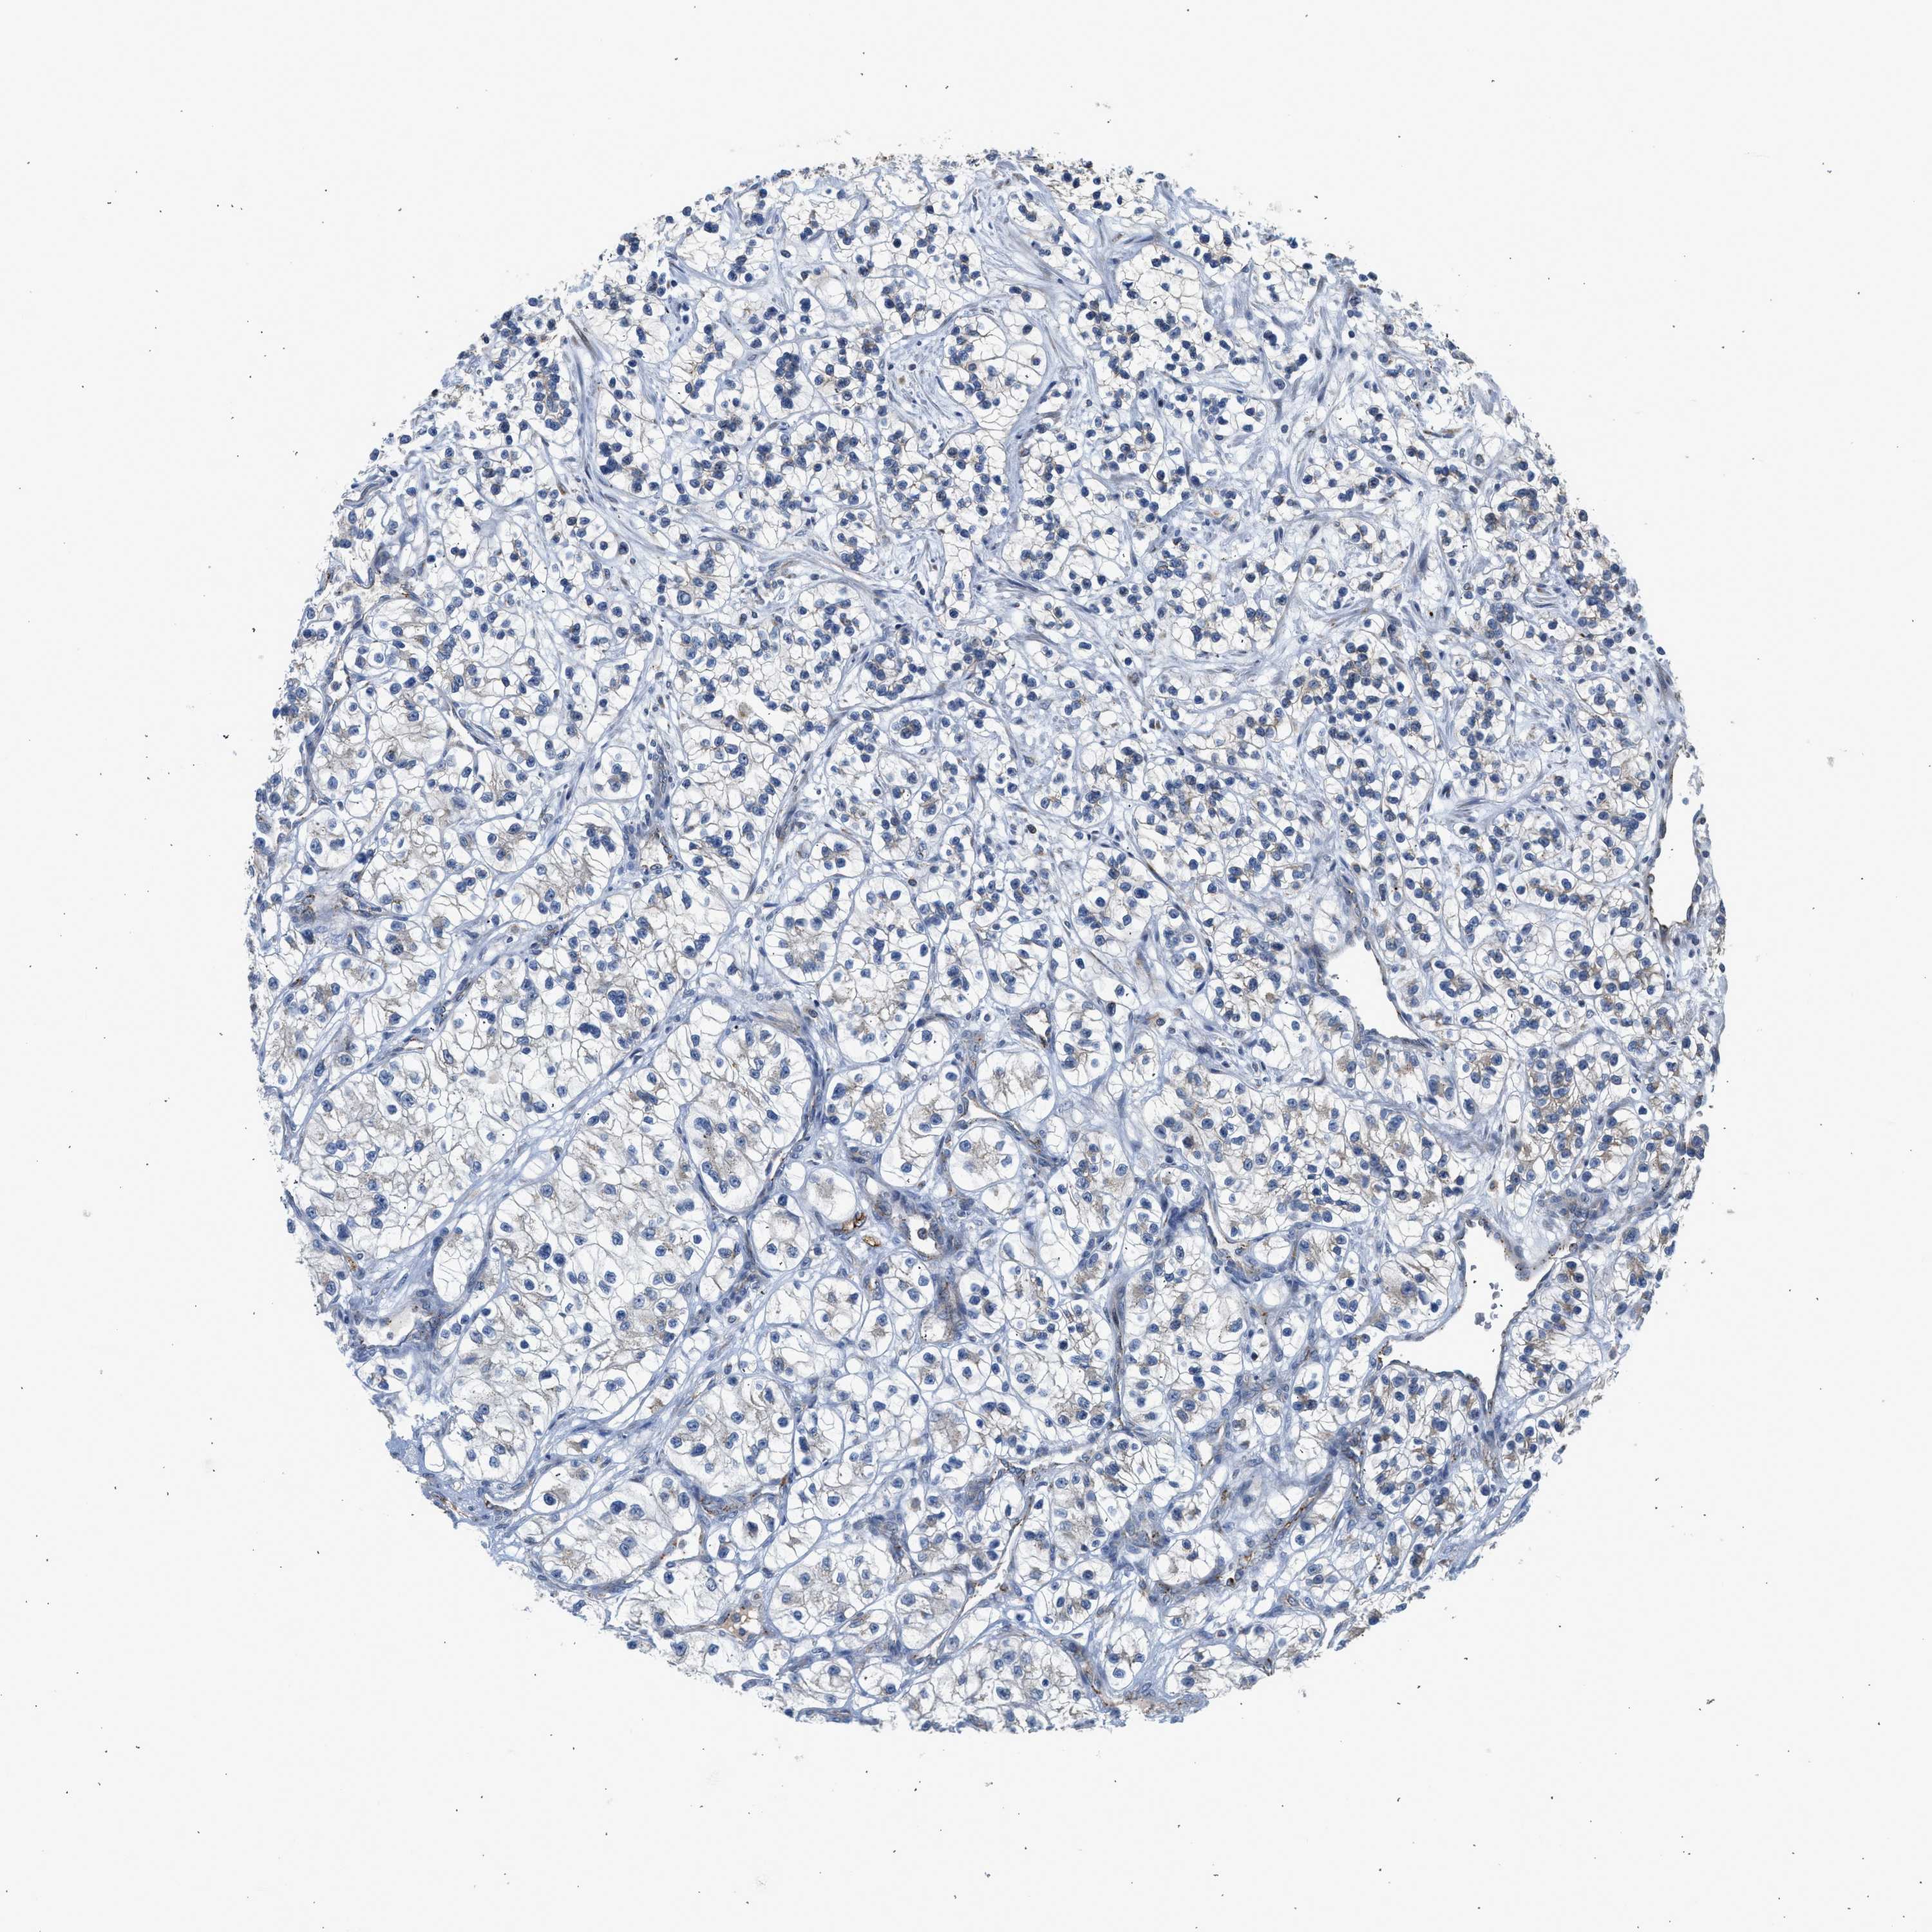

KIDNEY RENAL CLEAR CELL CARCINOMA (TCGA) - Interactive survival scatter ploti

The Survival Scatter plot shows the clinical status (i.e. dead or alive) for all individuals in the patient cohort, based on the same data that underlies the corresponding Kaplan-Meier plots. Patients that are alive at last time for follow-up are shown in blue and patients who have died during the study are shown in red.

The x-axis shows the expression levels (FPKM) of the investigated gene in the tumor tissue at the time of diagnosis. The y-axis shows the follow-up time after diagnosis (years). Both axes are complimented with kernel density curves demonstrating the data density over the axes. The top density plot shows the expression levels (FPKM) distribution among dead (red) and alive patients (blue). The right density plot shows the data density of the survived years of dead patients with high and low expression levels respectively, stratified using the cutoff indicated by the vertical dashed line through the Survival Scatter plot. This cutoff is automatically defined based on the FPKM cutoff that minimizes the p-score. The cutoff can be changed by dragging the vertical line or by entering a cutoff value in the square labeled "Current cut-off".

Under the Survival Scatter plot the p-score landscape (black curve; left axis) is shown together with dead median separation (red curve; right axis). Dead median separation is the difference in median mRNA expression between patients who have died with high and low expression, respectively. It is calculated as follows: median FPKM expression of dead patients with high expression - median FPKM expression of dead patients with low expression. This is intended to aid the user in visually exploring custom cutoffs and the associated p-scores and dead median separation.

Individual patient data is displayed and can be filtered by clicking on one or more of the category buttons on the top of the page. Categories describing expression level and patient information include: high, low, alive, dead, female, male and tumor stages. The scale of the x-axis can be toggled between linear and log-scale by clicking on the "x log" button. Mouse-over function shows TCGA ID, patient information and mRNA expression (FPKM) for each patient.

& Survival analysisi

Kaplan-Meier plots summarize results from analysis of correlation between mRNA expression level and patient survival. Patients were divided based on level of expression into one of the two groups "low" (under cut off) or "high" (over cut off). X-axis shows time for survival (years) and y-axis shows the probability of survival, where 1.0 corresponds to 100 percent.

PIM1 is not prognostic in Kidney Renal Clear Cell Carcinoma (TCGA)

Best expression cut offi

Based on the FPKM value of each gene, patients were classified into two groups and association between prognosis (survival) and gene expression (FPKM) was examined. The best expression cut-off refers the FPKM value that yields maximal difference with regard to survival between the two groups at the lowest log-rank P-value. Best expression cut-off was selected based on survival analysis .

When clicking on this number, the vertical dashed line indicating cut-off, the interactive survival plot, and the Kaplan-Meier curve will be adjusted to show results based on the best expression cut-off.

: 21.62

Median expressioni

Median expression refers to the median FPKM value calculated based on the gene expression (FPKM) data from all patients in this dataset. When clicking on this number, the vertical dashed line indicating cut-off, the interactive survival plot, and the Kaplan-Meier curve will be adjusted to show results based on the median expression.

: N/A

Median follow up timei

Median follow up time refers to the median time (years) after diagnosis with this type of cancer, based on clinical data from all patients in this dataset.

P scorei

Log-rank P value for Kaplan-Meier plot showing results from analysis of correlation between mRNA expression level and patient survival.

N/A

5-year survival highi

5-year survival for patients with higher expression than the expression cutoff.

For melanoma and glioma, 3-year survival is shown.

5-year survival lowi

5-year survival for patients with lower expression than the expression cutoff.

TCGA RNA samplesi

RNA-seq data is reported as average FPKM (number Fragments Per Kilobase of exon per Million reads), generated by the The Cancer Genome Atlas (TCGA) .

Normal distribution across the dataset is visualized with box plots, shown as median and 25th and 75th percentiles. Points are displayed as outliers if they are above or below 1.5 times the interquartile range. FPKM values of the individual samples are presented next to the box plot.

Average pTPM 22.6

Number of samples 521